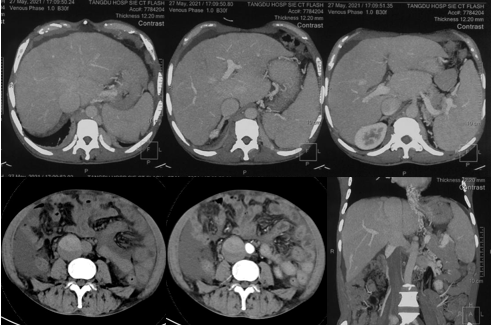

6月20日,患者及家屬懷揣著忐忑的心情來(lái)到西安國(guó)際醫(yī)學(xué)中心醫(yī)院找到韓國(guó)宏教授,韓教授詢問(wèn)病情后閱患者外院CT片,明確診斷布加綜合征,同時(shí)發(fā)現(xiàn)了一個(gè)新的問(wèn)題,在詢問(wèn)病史時(shí)了解到患者近一周雙下肢乏力伴腫脹明顯加重,遂立即安排了急診CT,證實(shí)下腔靜脈內(nèi)急性血栓形成!

6月22日,在韓國(guó)宏教授的帶領(lǐng)下,患者于消化介入診療中心行下腔靜脈開通術(shù)。術(shù)中可見(jiàn):下腔靜脈全段擴(kuò)張,膜性閉塞,腎靜脈平面以下可見(jiàn)血栓形成并伴有粗大的側(cè)枝靜脈,遂對(duì)狹窄段球囊擴(kuò)張并植入支架,術(shù)后下腔靜脈血流通暢,側(cè)枝消失。術(shù)后第2天,患者腹壁靜脈曲張幾乎消失不見(jiàn),走路也輕快了許多。明明只是薄薄的一層膜,為什么開通起來(lái)這么難?韓教授指出,盡管布加綜合征介入開通技術(shù)已使創(chuàng)傷降到了最低,但受到患者個(gè)體差異及醫(yī)療水平參差不齊的限制,仍有可能出現(xiàn)嚴(yán)重的并發(fā)癥,主要包括:心包積血、縱隔血腫、心包填塞甚至下腔靜脈撕裂引起的大出血等。而其發(fā)生率與術(shù)者的操作熟練程度及經(jīng)驗(yàn)有很大的關(guān)系。